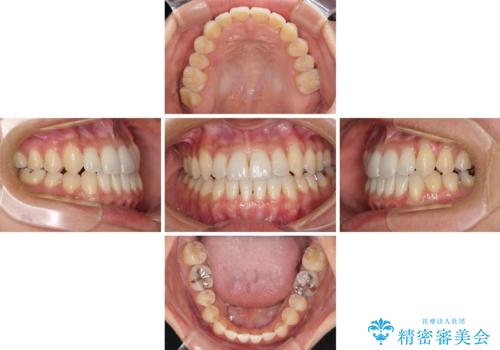

前歯のデコボコ インビザラインによる矯正治療

- 上下前歯の叢生と奥歯の反対咬合を気にして来院された患者様です。

インビザラインを用い、下顎はIPR(歯と歯の間を削る)と歯列全体を後方に移動させ、上顎は側方に拡大させることで歯列を改善していくこととしました。

骨格的に下顎が左側前方にずれているため、上下正中のズレや左右奥歯の咬み合わせを理想的な状態とすることは困難でした。